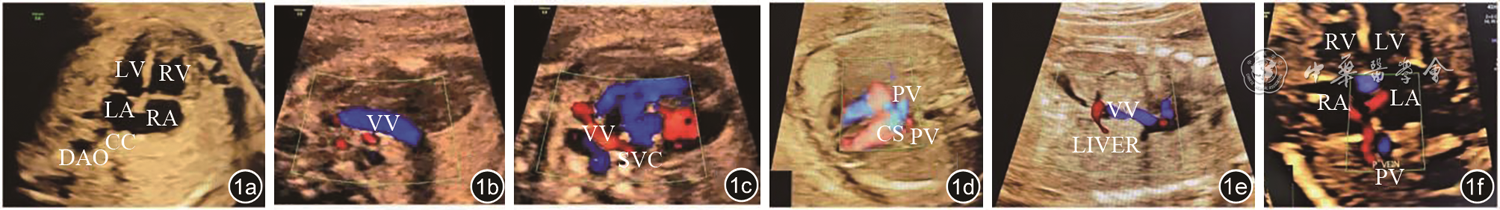

图1 肺静脉异位引流产前超声图像。图a为产前超声四腔心切面示左心房后壁光滑,左心房后方可见肺静脉形成的共同腔,左心房后壁空间指数增大;图b为垂直静脉;图c为完全性肺静脉异位引流(心上型)垂直静脉汇入上腔静脉;图d为完全性肺静脉异位引流(心内型)肺静脉形成共同腔后汇入冠状静脉窦;图e为完全性肺静脉异位引流(心下型)垂直静脉进入肝脏汇入门静脉;图f为部分性肺静脉异位引流(心内型)单只肺静脉直接汇入右心房注:LV为左心室;RV为右心室;LA为左心房;RA为右心房;DAO为降主动脉;CC为共同腔;VV为垂直静脉;IVC为下腔静脉;PV为肺静脉;LIVER为肝脏